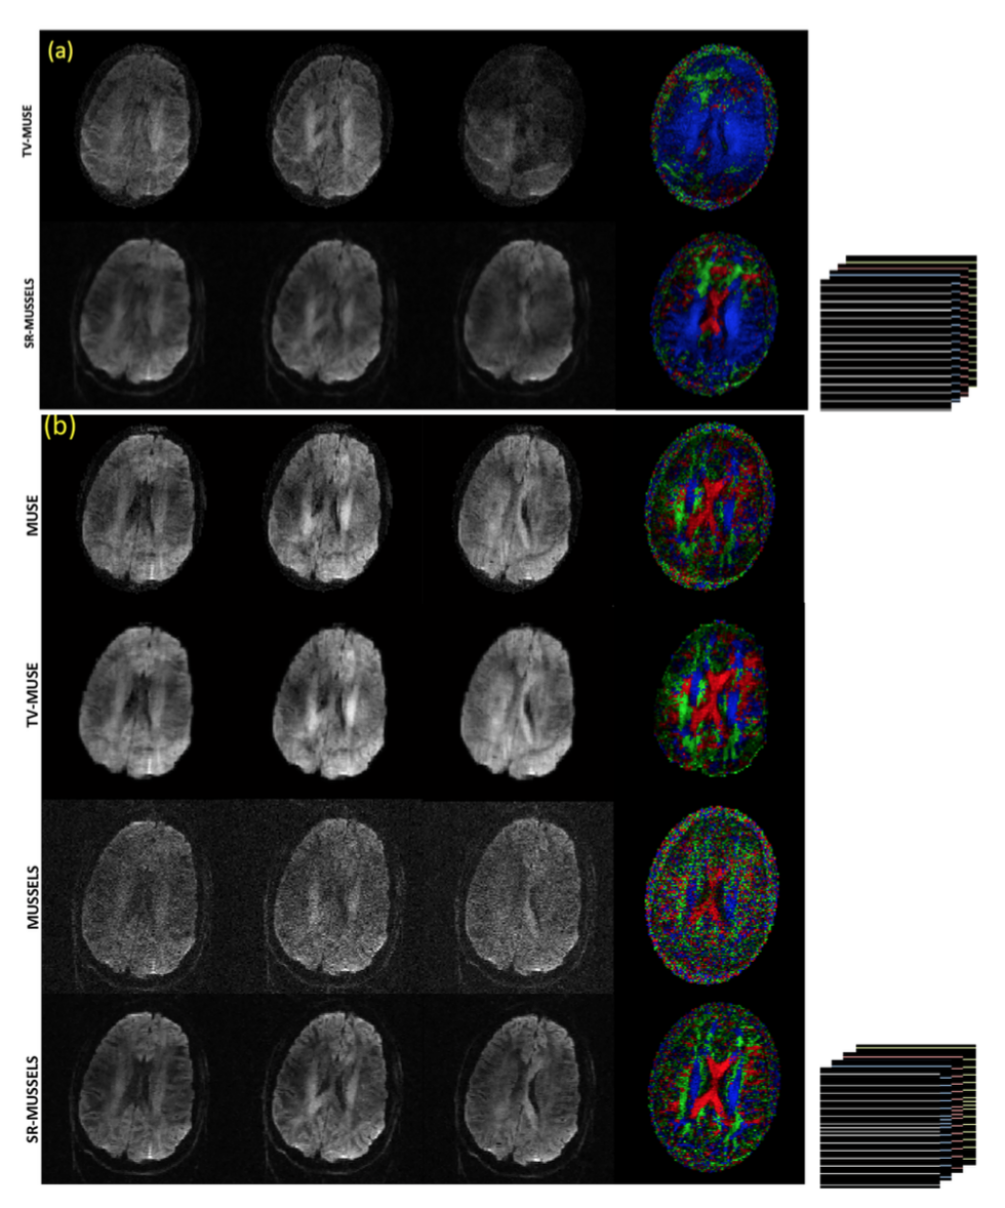

Regularized reconstruction for under-sampled multi-shot DWI

The previous experiments demonstrate the utility of MUSSELS to recover the fully sampled MS-DWI data. Here we show here that the regularized version of MUSSELS can be used to recover under-sampled MS-DWI data as well. For this purpose the 4-shot MS-DWI data was first under-sampled uniformly by skipping every other k-space lines from each of the shots. The top two rows of figure 8 shows the reconstruction of the 4-shot under-sampled MS-DWI data using TV-MUSE and SR-MUSSELS. This experiment highlight the situation where phase-based methods will fail. The inadequate unalising is evident in all DWIs reconstructed by MUSE. The regularized MUSSELS has performed reasonably well with significantly fewer artifacts seen visually in the reconstructed images. The color-coded FA maps generated from the six DWIs highlights the errors in the individual reconstructions. Interestingly, if the under-sampling pattern is changed slightly, the performance of both the methods improve significantly. The bottom rows of figure 8 shows the results of reconstruction where a non-uniform under-sampling pattern was employed. Specifically, the center k-space lines of each of the shots were kept intact. The improvement in the reconstruction results can be appreciated from the DWIs as well as the color coded FA maps. This behavior is not surprising and adds evidence to the fact that reconstructions from a slightly non-uniform under-sampling patterns provides more reliable results than a strictly uniform under-sampling pattern while using sparsity/low-rank -based reconstructions (33).

Fig 8: 4 shot under-sampled MS-DW data. (a) shows the TV-MUSE and SR-MUSSELS reconstruction of 3 DWIs reconstructed from uniformly under-sampled data. The under-sampling pattern is shown on the right side. (b) shows the unregularized as well as regularized MUSE and MUSSELS reconstruction of 3 DWIs reconstructed from non-uniformly under-sampled data. The under-sampling pattern used is included which shows that the center-k-space lines were kept intact for all the shots. The unregularized reconstructions also performed reasonably well with the non uniform under-sampling pattern.